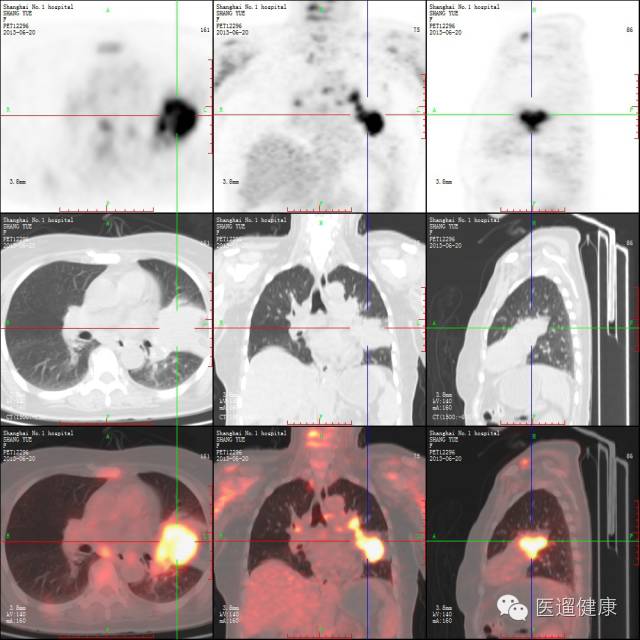

案例二、

病患:男,75岁,“咳嗽、咳痰伴左骶髂关节疼痛半月”CT平扫:右下肺占位。PET/CT检查目的:肺部病灶定性、了解全身情况。

右肺下叶软组织肿块,边缘分叶状,与右下胸壁相连,放射性浓聚,SUV最大值11.3

隆突下LN肿大,放射性分布浓聚,SUV最大值6.2

肝内多发大小不等结节状低密度区,放射性浓聚,SUV最大值9.8

骶骨骨质破坏,放射性浓聚,SUV最大值11.1

医生通过PET/CT检查得出结论:

右肺癌伴纵隔淋巴结、肝脏、骨转移(IV期)